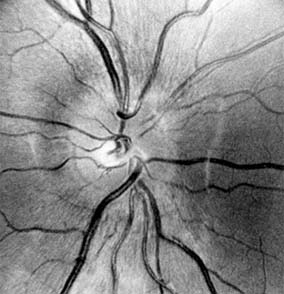

Figure 14-11

Figure 14-11: Retinal nerve fiber layer in demyelinating optic neuropathy of multiple sclerosis. The upper temporal nerve fiber bundles show multiple slit-like areas of thinning (arrows) representing retrograde axonal atrophy from subclinical disease in the optic nerve. Vision in the eye was 20/20.